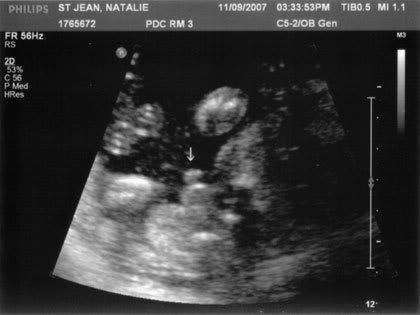

And the money shot! It’s a BOY, baby! And it was like every time she tried getting a photo of his spine… PENIS…. PENIS…. oh there it is again! LOL!!! Absolutely NO doubt about it, we have a little boy.

Then she goes to move down to measure the legs and says, “You wanted to know right?” Then she started checking the legs. I couldn’t see anything at first, my heart was pounding a little bit in excitement, then she says, “Looks like it’s a boy!” Sure enough baby had his legs wide open, and his little “bits” were dangling around. We got two photos of that – I only scanned the better one. But both show the two little bulges on top of one another like a snowman… the little balls and the little penis.

So then she started measuring the legs, got a photo of a foot sticking out, measured the spine. And every time she scanned back and forth his legs were wide open, showing off his boy parts. The tech actually apologised, “Sorry! Can’t help it, he has it all on display!” I just laughed.